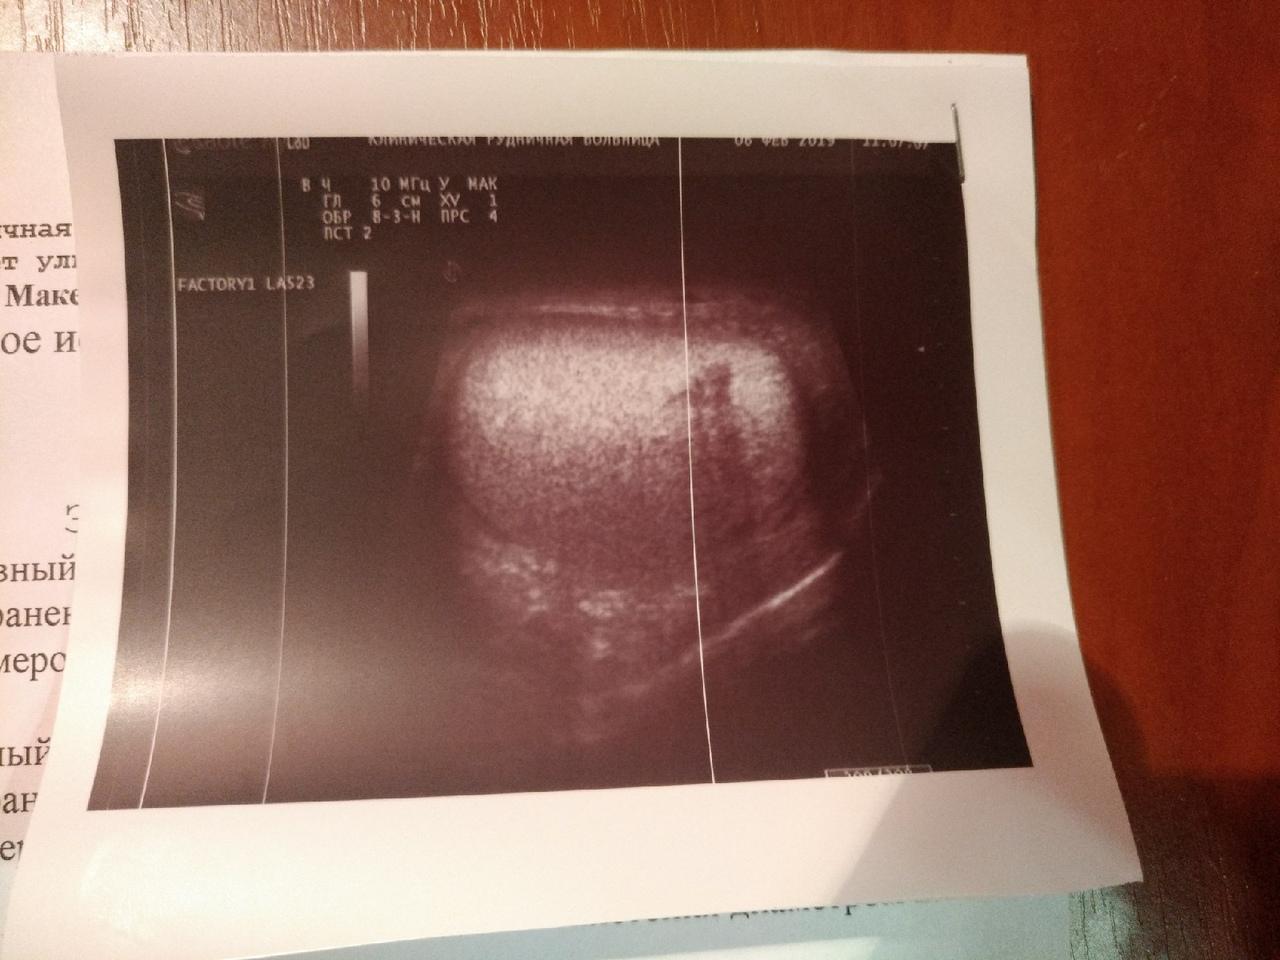

Год назад мне сделали операцию метод Мармара при варикоцеле. До сегодняшнего дня размер моего левого яичка не уменьшился в норму. Болей нет. Уплотнения есть, вены расширены, но, как мне сказали, незначительно. Всё указано в УЗИ.

Здравствуйте! Судя по результатам УЗИ в разные сроки.отмечается всё же динамика - уменьшение размеров яичка и придатка слева. Посоветуйтесь с Вашим урологом по поводу приёма препарата Детралекс для улучшения микроциркуляции. Удачи!